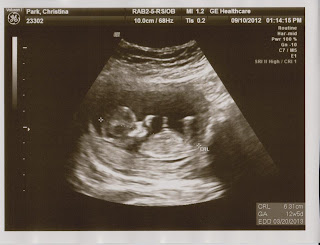

There was our child. Like nothing had been going on. Measuring exactly six weeks, meaning that his or her tiny heart (the size of a poppyseed) had just started beating in the last 48 hours. While we were mourning the loss, his life was actually just starting.

All I know is that on Thursday I gazed at a picture of my empty womb, and on Friday I have a healthy baby nestled there with a beating heart.